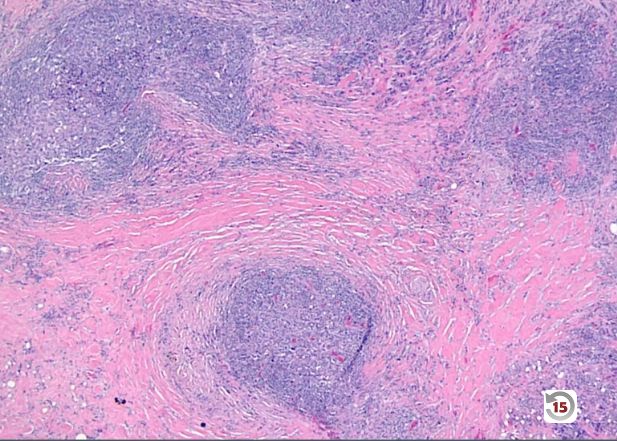

Which subtype of Hodgkin lymphoma is seen in the image below? _____